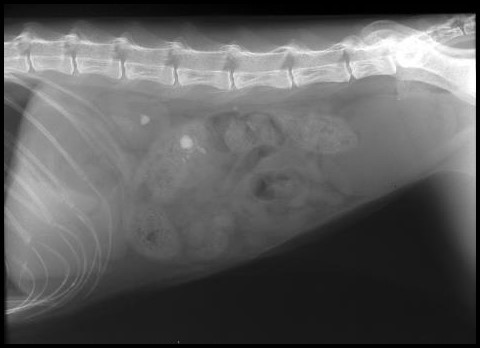

what is this?

Small kidney and abnormal ca

Was ist Das?

IVU

Mis-shapen – fibrotic

Small